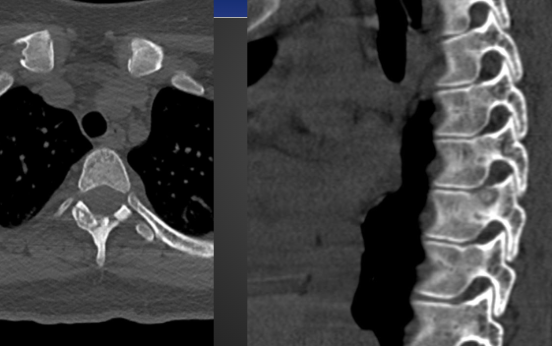

Giant Cell Tumor

-AKA Osteoclastoma

-Quasi malignant (80% benign, 5-8% of primary malignancies, 15% of benign osseous neoplasms)

-Most common at 20 to 40 years of age

Giant Cell common locations

-Knee (most common)

-Distal radius

-Proximal humerus

-Sacrum

Imaging Feature of Giant Cell Tumor

-Geographic lytic lesion eccentrically located within the metaphysis about the knee, without a sclerotic margin

-In long bone 90% will have subarticular extension

-80 to 90% will not show sclerotic margin

-Multiloculate and septated

-Expansile

-Imaging cannot differentiate malignant from benign

Giant Cell Tumor on X-ray